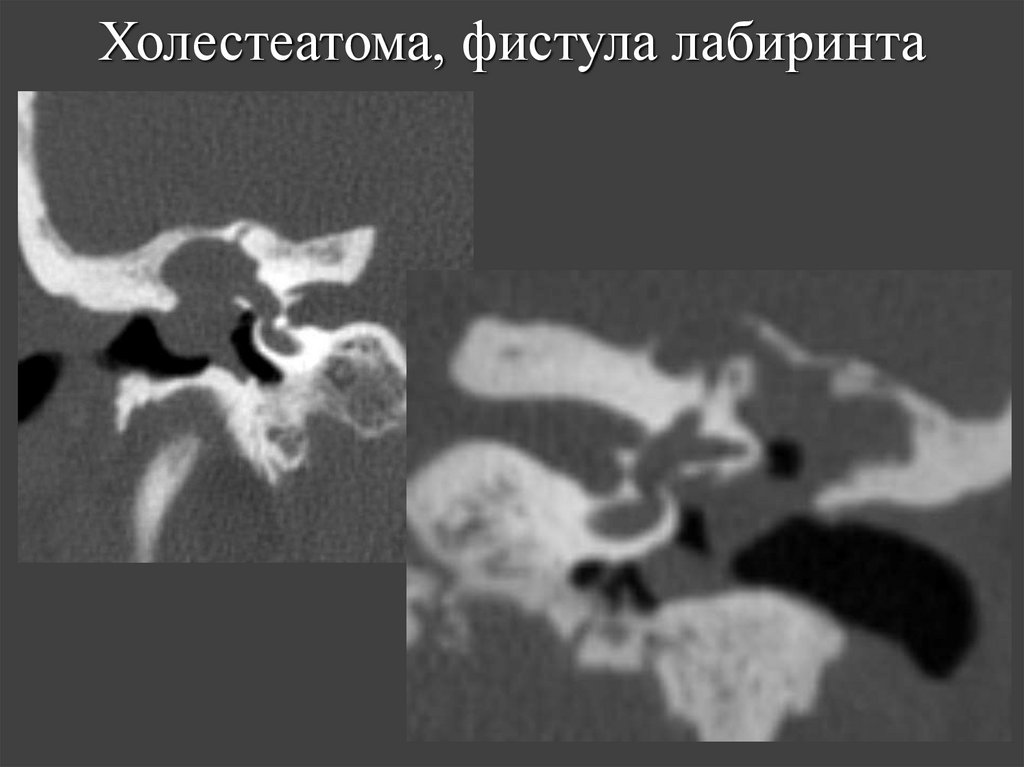

65. Холестеатома, фистула лабиринта

63. Осложнения холестеатомы, выявляемые на КТ

• Фистула лабиринта.

64. Фистула латерального полукружного канала